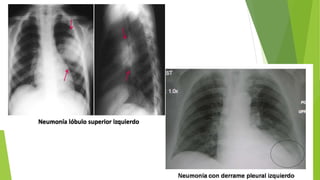

RADIOGRAFIA DE TORAX

• PRESENCIA DE INFILTRADO EN RX TORAX

• ASPECTO: consolidación lobar o segmentaria

DIAGNOSTICO ESTUDIO HISTOPATOLOGICO DELTEJIDO PULMONAR RADIOGRAFIA DE TORAX • PRESENCIA DE INFILTRADO EN RX TORAX • ASPECTO: consolidación lobar o segmentaria PRUEBAS COMPLEMENTARIAS • HEMOCULTIVO (+) para neumococo • Leucositos PMN >15000- 40 0000/ul o leucopenia